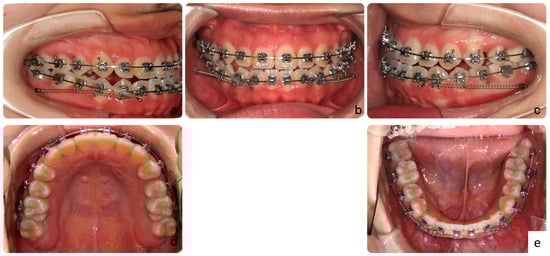

2.4. Treatment Progress